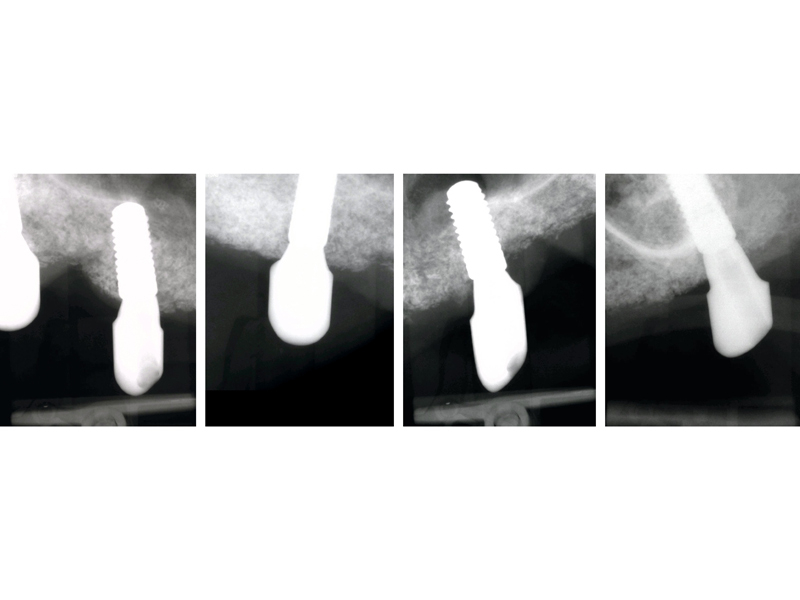

23/23 - Final x-ray one year after implantation 12/15/22/25

Full arch reconstruction of the maxilla with maxgraft® bonebuilder - Dr. M. Erbshäuser